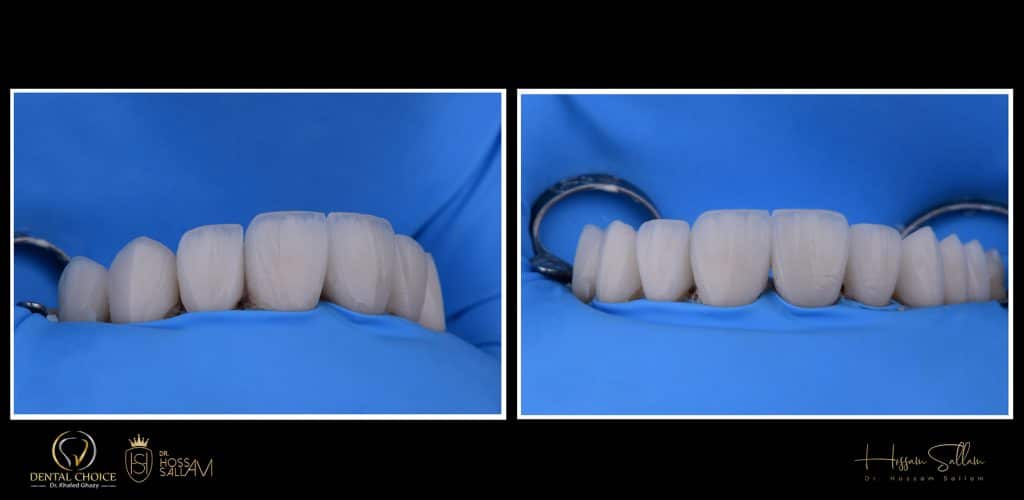

Two Centrals had been prepared as two separate crowns because they had been endodontic treated

and the rest had been prepared as veneers

Additional Silicone material is the best choice here to get the best details

i prefer using Veneer me

it helps me and save more time